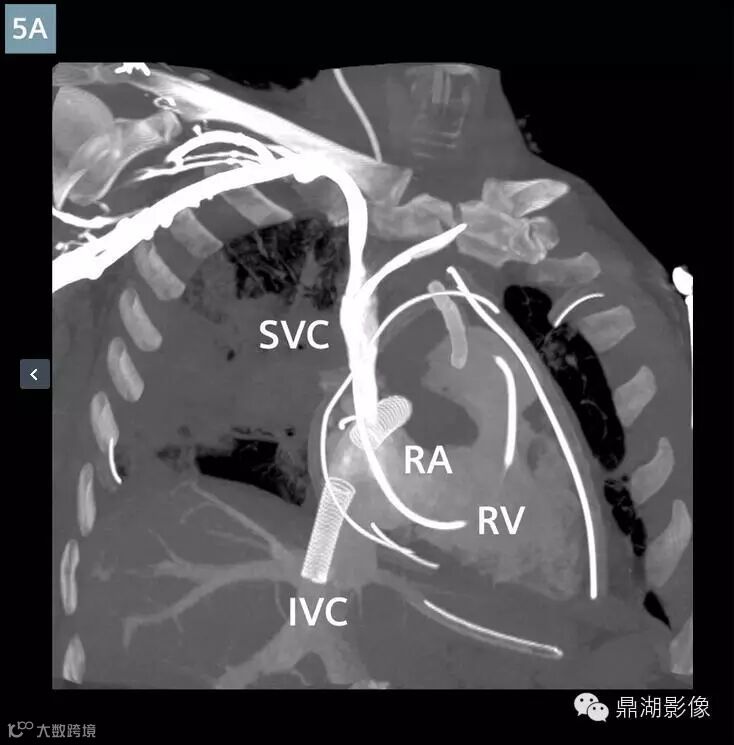

肺动脉CTA显示新的多发性肺栓塞和右动脉完全闭塞(图1)。左下叶肺动脉和静脉灌注一直持续(图3)。存在广泛右肺动脉梗塞(图2)。上腔静脉,右心房,右心室充满造影剂,造影剂回流进入肝静脉和下腔静脉(图5A)。主肺动脉CT值衰减大于250亨氏单位,这可以让医生确定扫描的诊断质量。ECMO系统和主动脉的分支未显影,体现了良好的团注时间(图4)。

Contrast-enhanced coronal oblique MPR(Fig. 5A) and VRT (Fig. 5B) image at the level of the right heart: Contrast injected via a right arm peripheral IV opacifies the superior vena cava (SVC), right atrium (RA), and right ventricle (RV). There is reflux of contrast into the hepatic veins (Fig. 5A) in the setting of elevated right heart pressures. Surgical drains, central venous catheters, and ECMO cannulae are in place.